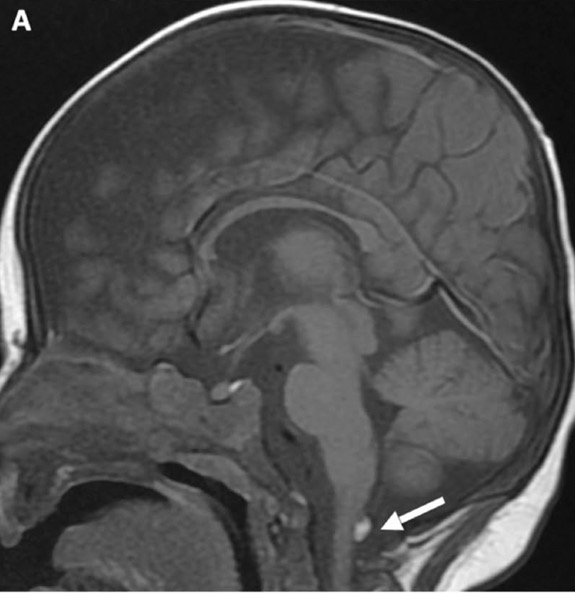

c. Lipomatose encéphalocraniocutanée (ECCL): peau, yeux, SNC)

ECCL: